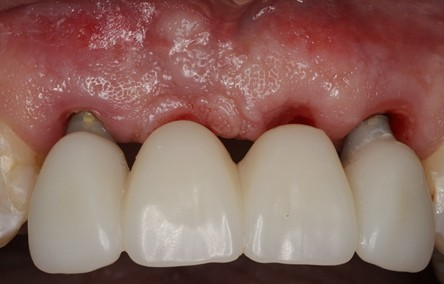

Not all clinical situations present us with ideal immediacy outcomes and staging may be the only option. The following case presented with initial plan extract teeth and immediately place implants with immediate fixed temporary. Due to lower stability at implant #7, we decided to avoid temporalization until at least 2 mo post implant placement.

Immediate implants were placed and patient was given an Essix retainer to wear for at least 6 weeks post implant placement.

Since temp shells were already fabricated, we were ready to pick up our temporary prosthesis using non-engaging temporary abutments.